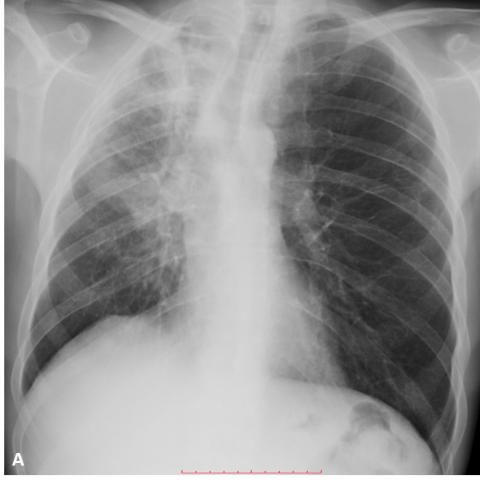

胸部X线片显示右上叶和中叶支气管实变,右斜裂膨出(图1)。

图1 实变伴支气管充气征,几乎完全占据了右上叶和部分中叶